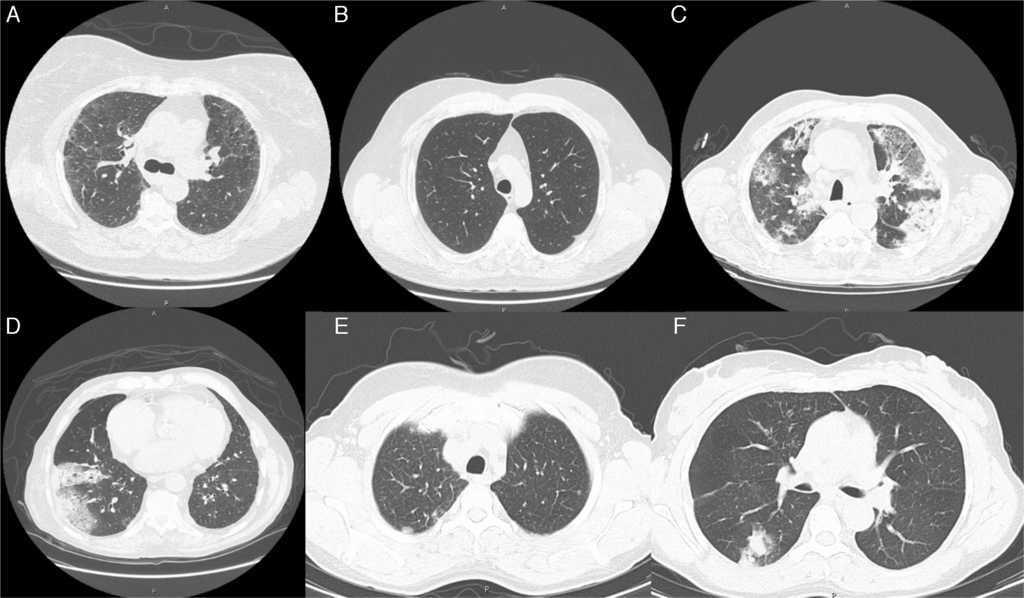

Radiological imaging of the chest, especially HRCT, was demonstrated to be the best tool in the diagnostic evaluation of patients with suspected small airways disease.8, 9 Chest radiography demonstrates normal findings or mainly hyperinflation in purely obstructive bronchiolar lesions such as constrictive/chronic bronchiolitis. In other primary bronchiolar disorders, small nodules or reticulonodular infiltrates (Figure 1A) may be observed.10 Features of bronchiolar disease on HRCT can be broadly categorized into direct and indirect signs.8, 9 Direct CT findings of bronchiolar disease include bronchiolar wall thickening, bronchiolar dilatation and luminal impaction that affect airways directly visible in the lung periphery.11 Bronchiolar wall thickening may occur due to inflammation or fibrosis. Bronchiolar luminal impaction with secretions or fibrotic material manifests as nodular and linear branching centrilobular opacities on CT. The “tree-in-bud” pattern represents a form of bronchiolar impaction in which branching linear structures have more than one contiguous branching site.9 Indirect signs of bronchiolar disease on CT include subsegmental atelectasis and air trapping.9, 10 In bronchiolar diseases, the mosaic pattern is caused by hypoventilation of alveoli distal to bronchiolar obstruction, which leads to secondary vasoconstriction and is seen on CT scans as areas of decreased attenuation.12, 13

Figure 1. Radiological features (Chest CT images) observed in some of the enrolled clinical cases. (A) Image revealing reticularnodular infiltrates, associated with areas of ground glass opacities. These features are consistent with UIP pattern and can be observed in various types of bronchiolitis, such as obliterative, constrictive, chronic and follicular bronchiolitis. (B) Diffuse micronodular pattern usually present in conditions related to tobacco, particularly in cases of respiratory bronchiolitis. A centrilobular emphysema in the upper lobes and thickened bronchial walls are also noted. (C) Extensive parenchymal changes, densification with areas of ground-glass bilaterally and (D) areas of consolidation associated with air bronchogram. These patterns can be found in various types of bronchiolitis, such as obliterative and constrictive bronchiolitis. (E) Subpleural nodule in the left upper lobe which may be associated with respiratory or obliterative bronchiolitis. (F) In the upper segment of the right lower lobe, a grossly nodular densification is observed, which may be present in almost all the histopathological types of Bronchiolitis.

In our sample, radiological findings were varied, and as discussed above, the most common patterns were pulmonary nodules and lung masses in 22.4% of patients (Figure 1E), ground glass opacities in 18.9% (Figure 1A, C and F), micronodular pattern or presence of interstitial reticulation (Figure 1B) in 10.6%, and pneumothorax was present in 23%. As mentioned, a small amount of patients had normal radiological study (2.8%).